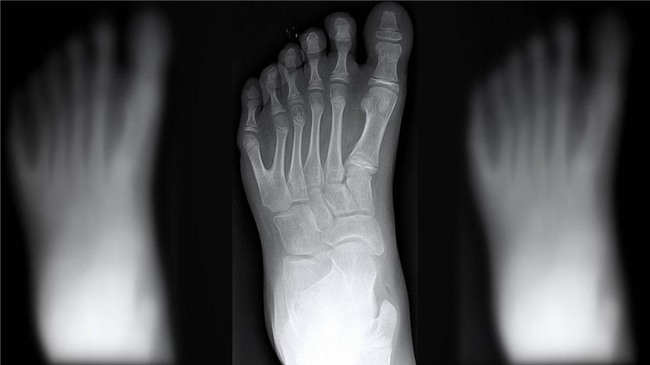

Cậu bé chào đời tên Vinicius, được sinh ra với mỗi bàn tay, bàn chân đều có 6 ngón.

Tình trạng gây ra sự xuất hiện bất thường của gia đình De Silva được gọi là polydactyly. Kì lạ là tình trạng này ảnh hưởng đến khoảng một trong 1000 người. Trong khi đó, cả gia đình dòng họ De Silva có tới 14 người như vậy. Nếu mẹ hoặc cha mang gen gây ra tình trạng polydactyl thì đứa con sinh ra sẽ có 50% khả năng có 6 ngón tay, chân trên 1 bàn như thế.

Cậu bé mới chào đời tên Vinicius, được sinh ra với mỗi bàn tay, bàn chân đều có 6 ngón.

Tiến sĩ Laura Lettice giải thích: "Có rất nhiều đột biến dẫn đến tình trạng này, nhưng đa phần chỉ là có thêm 1 ngón tay hoặc 1 ngón chân. Còn với gia đình De Silva thì họ có tới 2 ngón tay, 2 ngón chân và ở rất nhiều người”.

Tình trạng gây ra sự xuất hiện bất thường của gia đình De Silva được gọi là polydactyly.